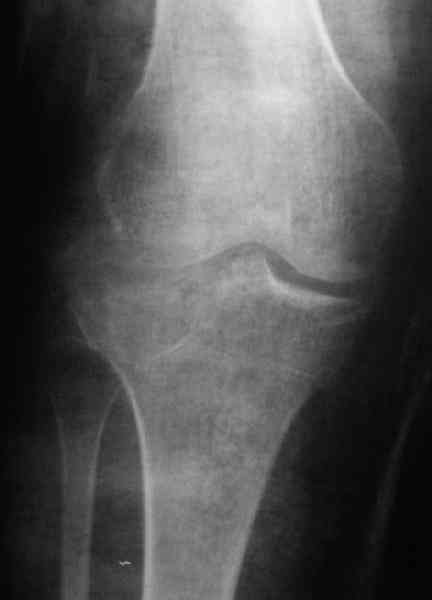

Re: Застарелый перелом 41С3

Дорогой коллега, застарелых переломов, во первых, не бывает. Они бывают сросшиеся, не сросшиеся и т.п. Во вторых, эндопротезирование на данном этапе технически очень затруднительно. Я бы предложил два варианта, первый - это консервативное лечение, с разгрузкой сустава, ортезированием и лечебными блокадами или второй - оперативный - ЧКДО аппаратом Илизарова на бедро - голень, растянуть сустав, попытаться, если перелом еще не консолидировался, исправить ось. Во всяком случае, на фоне дистракции легче провести разработку движений.

Уважаемый Ростислав. Спасибо что поправили, это у нас по старой привычке, "застарелый" наверное правильно будеть "неправильно вялоконсолидируюшаяся перелом" или есть еще другие варианты, надо подумать.

По тактике лечения, более импонирует второй вариант, но наружная плато расколота и туда при нагрузке внедряется н/мышелка бедра, поэтому после дистракции как репонирвать: или стяжными винтами, или изогнутами спицами или субхондральная костная пластика?

Отправитель: А..П.Ким 18 Апрель 2008, 15:55

Уважаемый Абдурашид. Если нет противопоказаний , то из оперативных способов, я бы рекомендовал следующие: Полное замещение наружного мыщелка аллотрансплантатом либо открытая репозиция с элевацией и замещение дефекта ауто или аллокостью. В Ваших условиях , я бы рекомендовал второй способ. Во-время элевации необходимо разъединить фрагменты со стороны сустава ( надсечь скальпелем по линиям перелома, а затем тонким остеотомом их разъединить. При помощи долота произвести неполную остеотомию ( захватите не менее 1,5 - 2 см губчатой кости и поднять фрагменты, визуально отрепонировать и фиксировать 2-3 спицами. Дефект заместить костным ауто или аллатрансплантатом. Окончательная стабилизация пластиной ( лучше с угловой стабильностью, либо АВФ - позволит спокойно устранить угловую деформацию.

Недавно поступила больная через 1,5- 2 месяца.